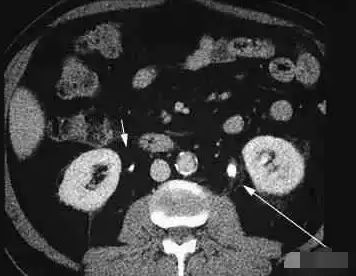

宝宝19个月的时候,家长发现孩子总是尿裤子,直到有一天,家长觉得不对劲,立马带着孩子去了医院,到医院检查发现宝宝的左肾多发性结石,右肾还有积水,医生建议马上手术。

家长不知道为什么宝宝这么小,肾里就会有那么多的结石?医生说:“从孩子的发育状况来看,可能是因为孩子长期补钙造成的,使尿钙升高而形成结石?!?/p>